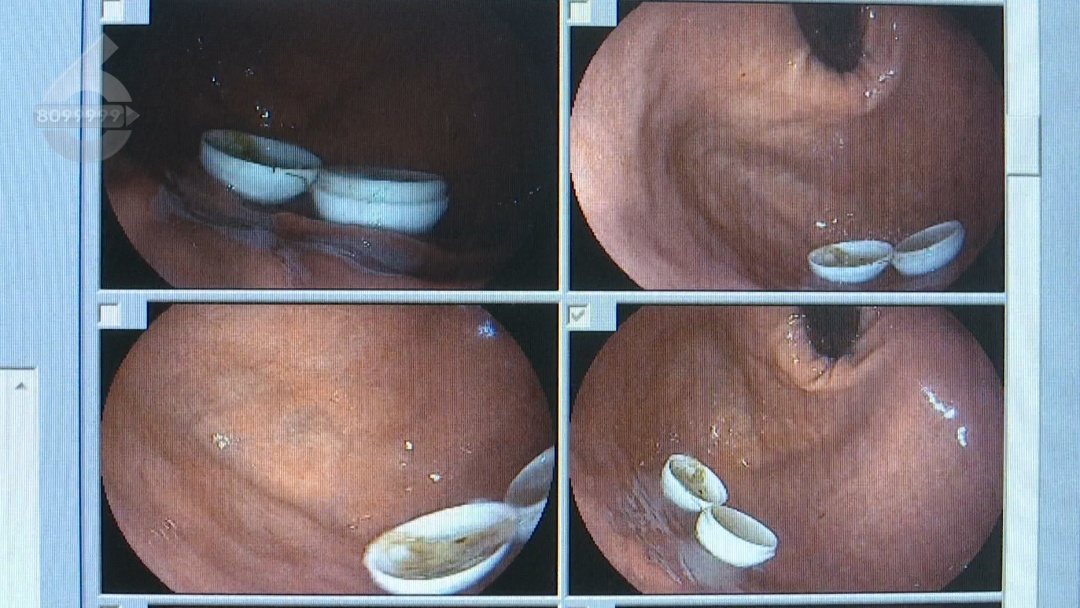

了解患者情况后,医生立即安排胃镜检查,发现患者误食的塑料球壳直径约2厘米,经过肠胃蠕动已经分离成了两瓣。

因为球壳直径比较大

没有办法通过幽门进入小肠

顺次进入到结肠排出体外

于是

医生用医用钳小心尝试

经过10多分钟的操作

分两次将塑料球壳取出